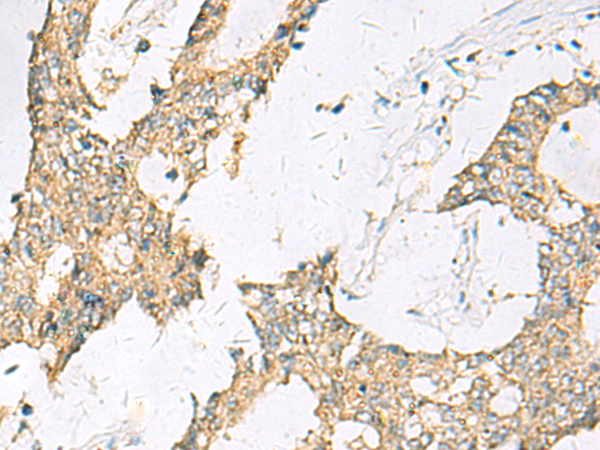

ELISA, IHC |

IHC positive control: |

Human cervical cancer and Human colorectal cancer |

IHC Recommend dilution: |

50-100 |